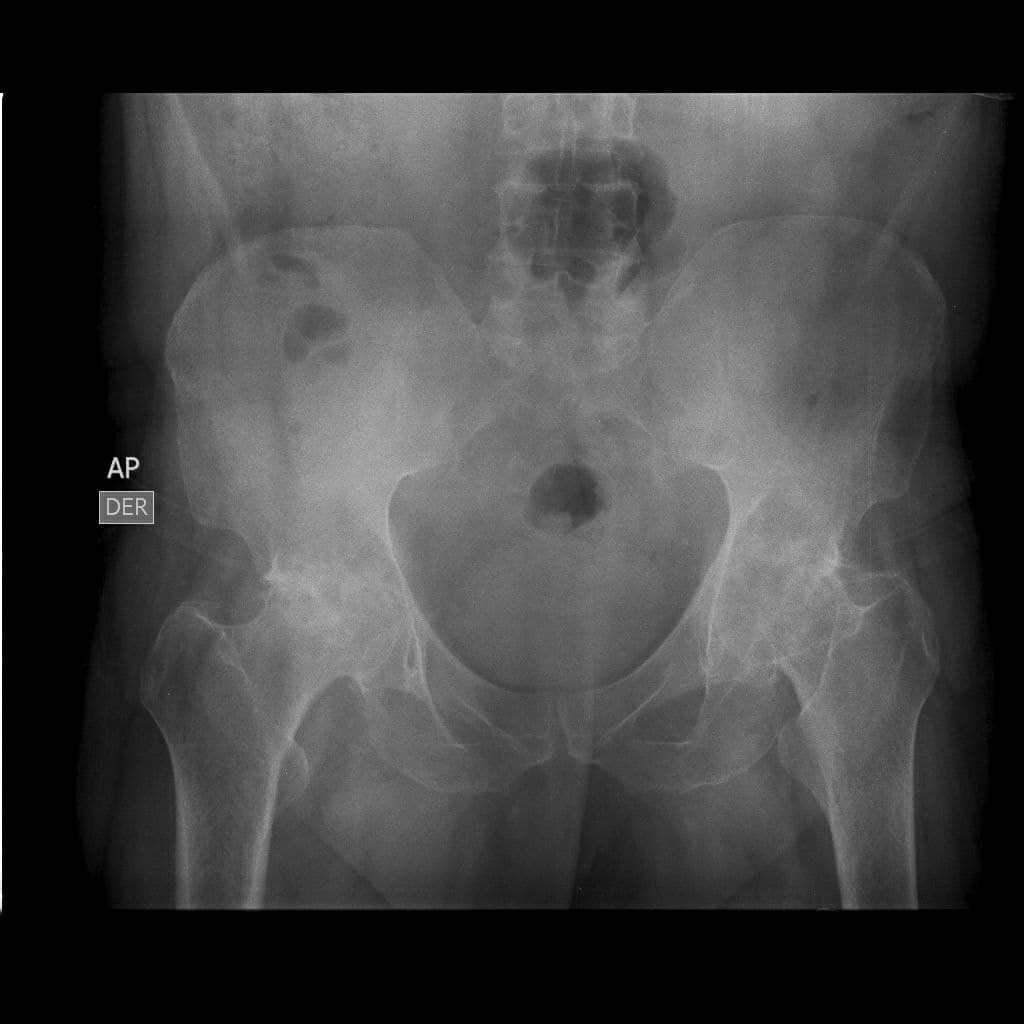

My father has grade III coxarthrosis in both hips and has lost his left femoral head, which causes severe pain and limits his mobility. He needs 2 hip prostheses as he could become disabled. The total cost of both interventions and prosthesis is $22000. Your support is invaluable